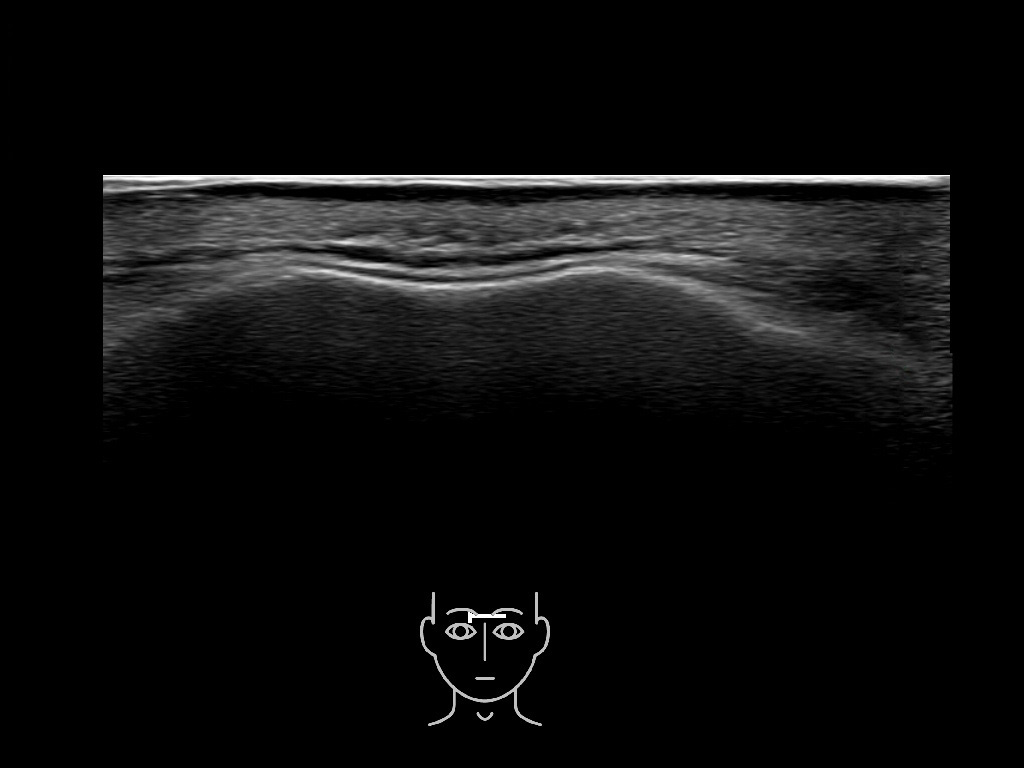

In this section you will learn more about the different layers of the face with the use of ultrasound. When you click on the secondary ultrasound image, you will see the different structures as an overlay. This will help to train yourself to recognize the different layers of the face.

Study the first image to recognize the different layers. If you are sure about the layers, swipe to the second image to view the answer (if applicable).